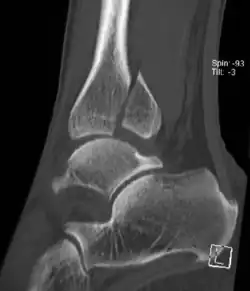

Bei Skelettanomalien und nach alten Brüchen, besonders aber bei Beteiligung der unteren tragenden Schienbein-Gelenkfläche durch den Bruch, kann eine Computertomographie (digitale Röntgenschichtuntersuchung) Klarheit über den Bruchverlauf verschaffen. Die Computertomographie hat eine wichtige Bedeutung, um eine Gelenkflächenbeteiligung und die Form eines posterioren tibialen Fragmentes (Volkmann-Dreieck) zu beurteilen. Bandschäden und Knorpelschäden z. B. am Sprungbein können gut mit einer digitalen Kernspintomographie untersucht werden.

Die Schädigung der Syndesmose kann in zwei Variationen erfolgen: Entweder zerreißen beide Syndesmosenbänder (und Teile der Membrana interossea cruris bis in Höhe der Fibulafraktur). Viel häufiger zerreißt jedoch das vordere, schwächere Syndesmosenband, und das hintere (stabilere) bleibt erhalten; dafür reißt der Bandansatz knöchern am unteren Schienbein breitflächig aus. Hierzu tragen Stauchungskräfte des Talus gegen die distale Tibiagelenkfläche bei. Diese Abrissfraktur mit der Bezeichnung Volkmann’sches Dreieck (oder Volkmann-Dreieck) ist bei Weber B möglich und bei Weber-C-Frakturen sehr häufig sowie die Ursache für eine komplette Gabelinstabilität des oberen Sprunggelenks (siehe Abb.).